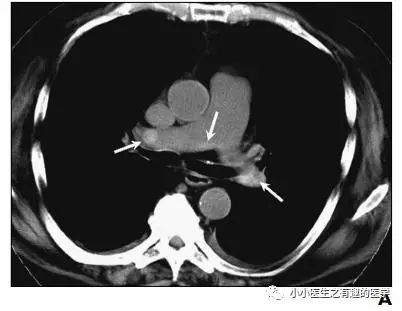

作者单位:Department of Radiology, University of Washington MedicalCenter, University of Washington School of Medicine(华盛顿医科大学)。

翠花上菜,学者上图。

发现嫌疑犯,立即逮捕。

增强CT对比,一目了然。

上面的患者,增强CT放大了。

下面是另外一个

星号的地方。

2.Kanne J P, Gotway M B, Thoongsuwan N, et al. Six cases of acute central pulmonary embolism revealed on unenhanced multidetector CT of the chest.[J]. Ajr American Journal of Roentgenology, 2003, 180(6):1661-4.